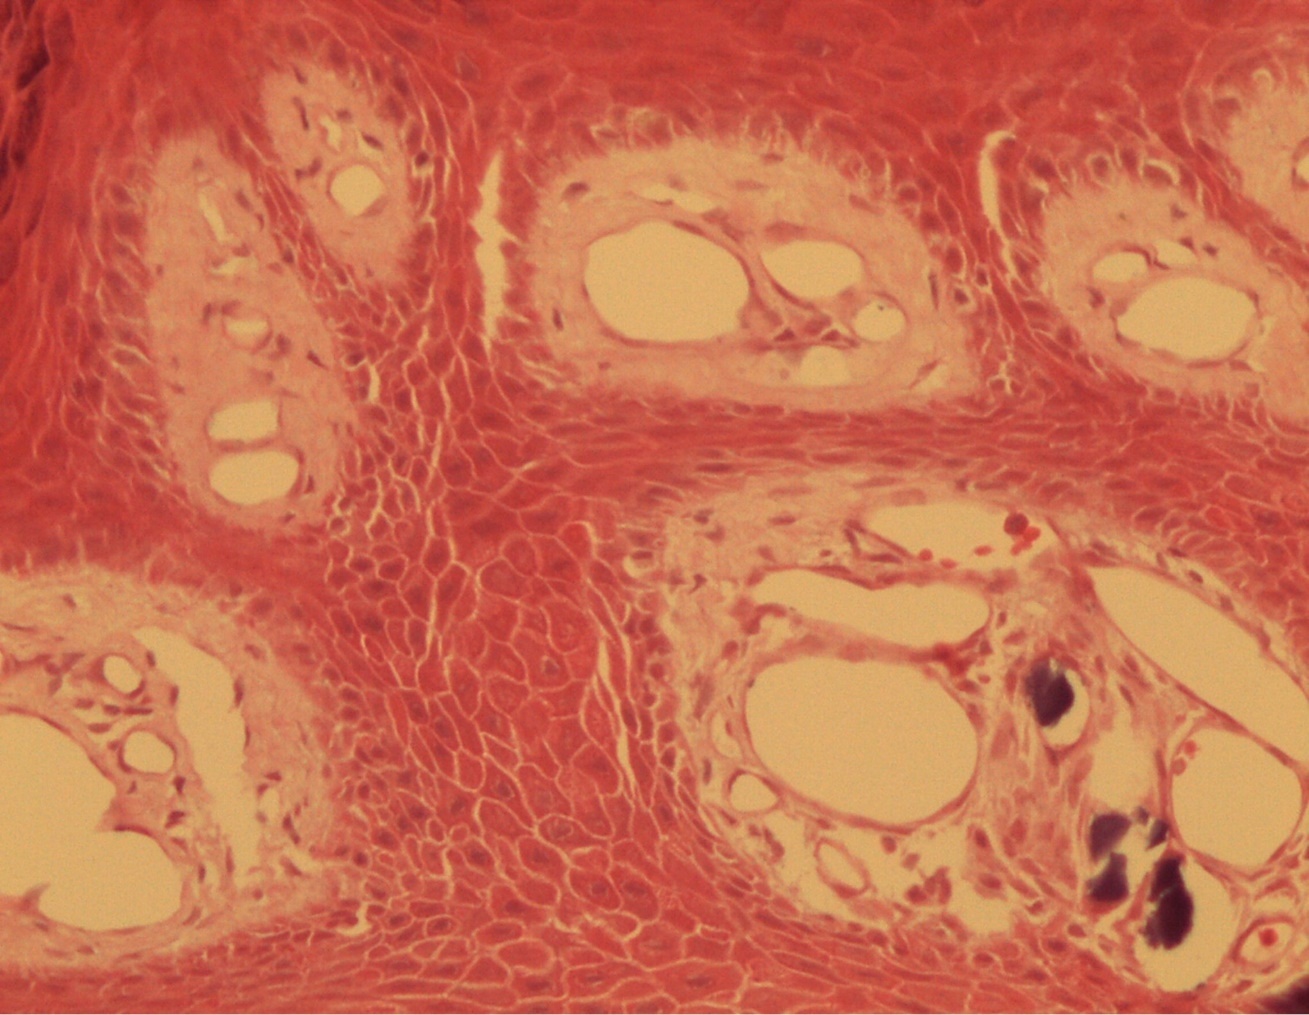

A 9-year-old male patient who was treated in the dermatology service for a progressively growing keratotic nummular dermal lesion on the right knee. With the clinical judgment of viral wart, the lesion was removed. In the Pathology Service, a nummular keratotic lesion of 0.5 cm in maximum dimensions was received, which crackled when cut. Figure 1, Figure 2, Figure 3, Figure 4, Figure 5

Figure 4.Presence of calcium deposits in the dermal vessels. Detail. HE 400x.